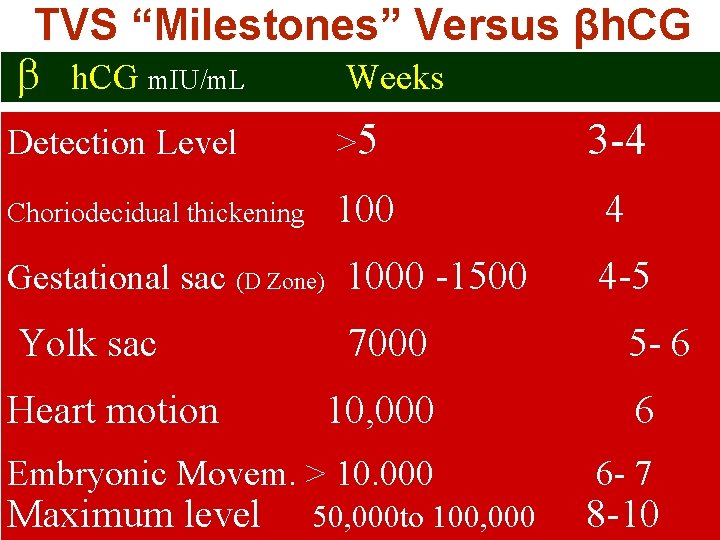

What Is The Most Common Presenting Symptom Of A Complete Molar Pregnancy? A. Hyperemesis B. Bilateral enlarged theca lutein cysts C. Vaginal bleeding D. Uterine enlargement> than expected for GA E. Pregnancy-induced hypertension

What Is The Most Common Presenting Symptom Of A Complete Molar Pregnancy? A. Hyperemesis 10% B. Bilateral enlarged theca lutein cysts 30% C. Vaginal bleeding 85% D. Uterine enlargement> than expected for GA 40% E. Pregnancy-induced hypertension 1%

How Is Complete Mole Diagnosed? U/S is helpful in making a pre-evacuation diagnosis but the definitive diagnosis is made by histological examination. U/S: Early detection reduced from 16 weeks (passage of vesicles) to 12 ws βh. CG levels > 2 multiples of the median may be of value in the diagnosis RCOG Guideline No. 38 ; 2010

U/S& βh. CG Definite diagnosis on first U/S examination ØU/S alone: 68% ØU/S + βh. CG > threshold of 82, 350 m. IU/m. L: 89% Disaia &Creasman Clinical Gynecological Oncologym 7 th edd. 2007

TVS “Milestones” Versus βh. CG m. IU/m. L Weeks Detection Level >5 3 -4 Choriodecidual thickening 100 Gestational sac (D Zone) 1000 -1500 Yolk sac Heart motion 7000 4 4 -5 5 - 6 10, 000 6 Embryonic Movem. > 10. 000 6 - 7 Maximum level 50, 000 to 100, 000 8 -10